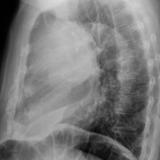

Case 8b Thymoma Lat

Date: 03/27/2009

Views: 14090